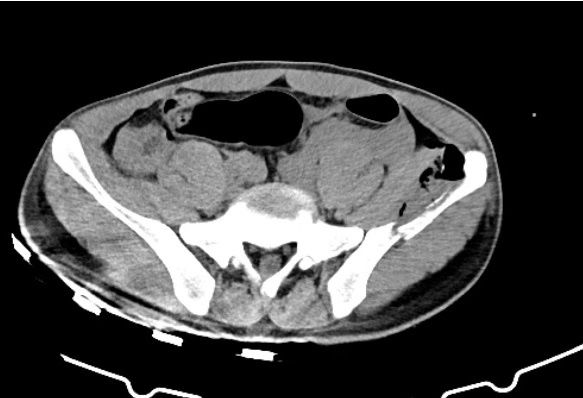

后车把手撞击腰部出现疼痛三小时来我院就诊,行ct检查提示右肾破裂,伴

右肾破裂伤伴肾周血肿形成 3.全身多发骨折4.肺挫伤,此时患儿